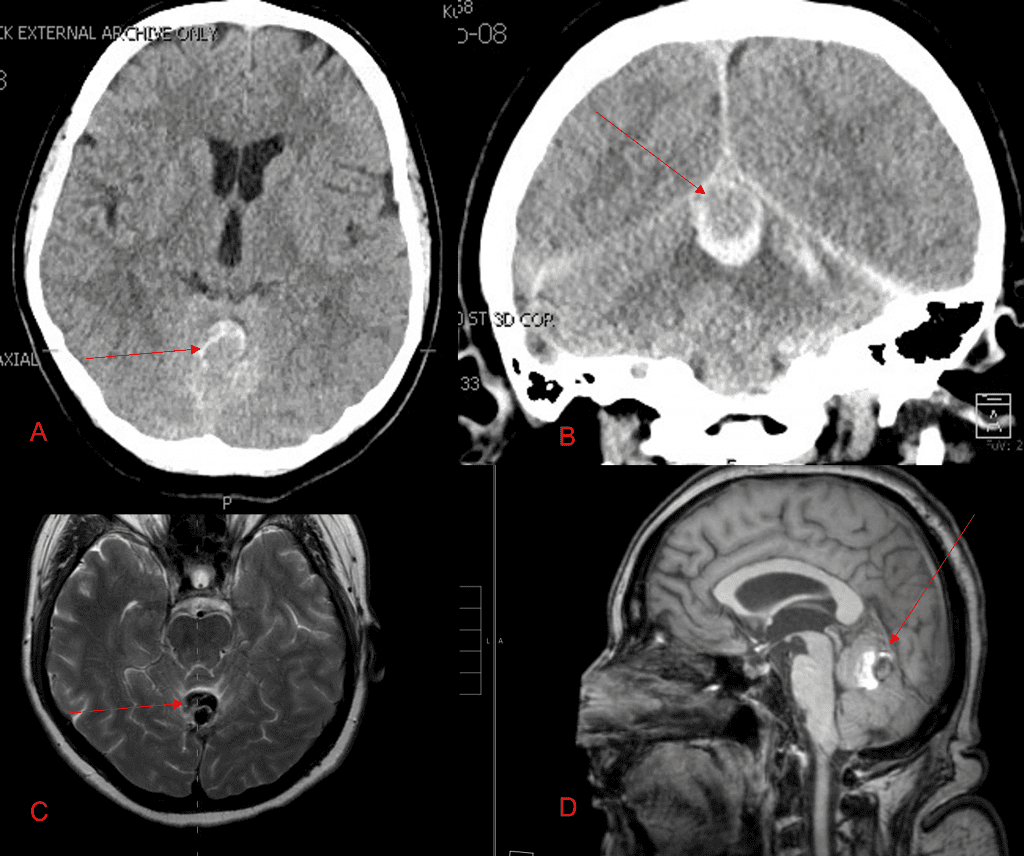

A 55-year-old woman presented with acute onset of severe headache, and possible witnessed seizure. Imaging confirmed intraventricular hemorrhage primarily focused within the fourth ventricle with diffuse […]